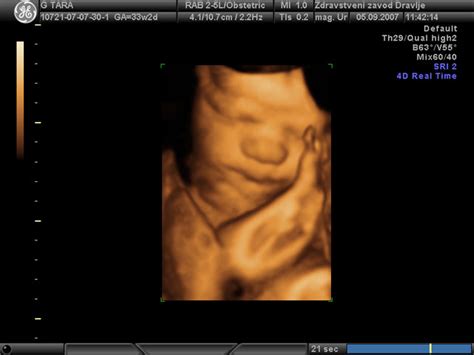

V večini primerov med zdravo nosečnostjo zadostujeta dva ali trije ultrazvočni pregledi. Če se ginekolog odloči za ultrazvok, se bo najprej pogovoril z vami. Pri tem morate vedeti tudi, da zdravstvena zavarovalnica pokrije le stroške za določeno število ultrazvočnih pregledov. Najbolje, da se glede tega čim prej pozanimate. Za podrobno diagnostiko se uporablja tudi 3D ultrazvok, ki ste ga morda že imeli. V večini primerov gre pri tem zgolj za previdnostni ukrep in ni razloga za zaskrbljenost.